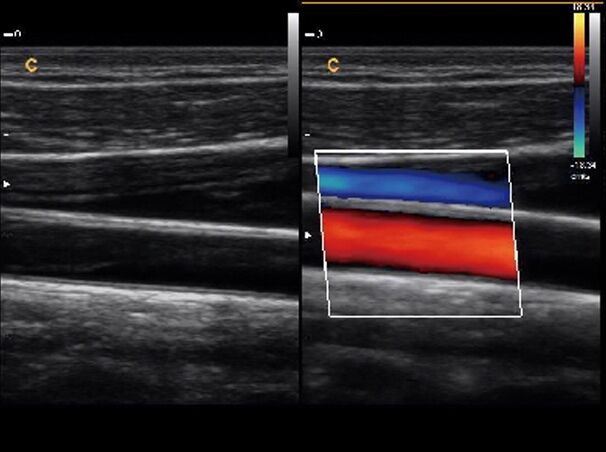

Veterinary Ultrasound Chison Ebit 30 Color Doppler & Micro-Convex Probe

Sale price$ 10,085.99

Regular price$ 12,299.99

Veterinary Ultrasound Chison Q9 Color Doppler & Micro Convex Small Animals Probe

Sale price$ 35,974.21

Regular price$ 43,870.99

Veterinary Ultrasound Chison Q9 Color Doppler & Micro-Convex Small Animals Probe

Sale price$ 8,199.18

Regular price$ 9,999.00

Veterinary Ultrasound Color Doppler 15" High Quality w/ Micro-Convex & Linear

Sale price$ 8,199.18

Regular price$ 9,999.00

Veterinary Ultrasound Color Doppler 15" High Quality W/ One Probe, USA Warranty

Sale price$ 5,739.18

Regular price$ 6,999.00

Veterinary Ultrasound Color Doppler, Quality Continuous Wave CW & Two Probes, C7

Sale price$ 10,659.18

Regular price$ 12,999.00

Veterinary Ultrasound Color Doppler, Quality Continuous Wave CW&Two Probes, C7

Sale price$ 6,559.18

Regular price$ 7,999.00